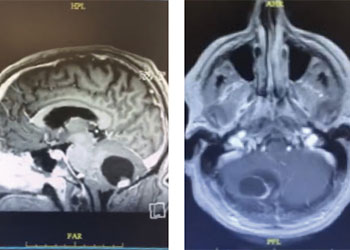

Endovascular:

Hydrocephalus and Brainstem Tumor

Author: Jonathan L. Brisman M.D., F.A.C.S., Read More!